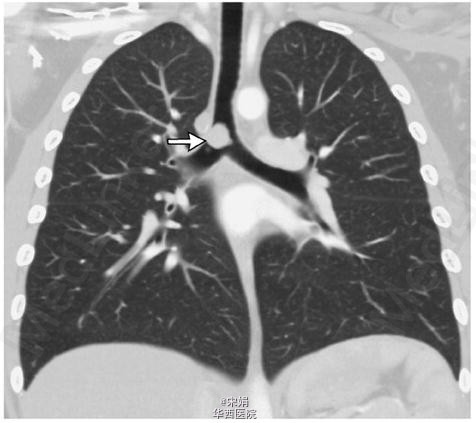

10岁小女孩,因发作性喘息,呼吸困难,进行性活动耐量下降9月就诊。既往体健。体格检查:双肺呼气相中度哮鸣音。初步诊断为哮喘,予以常规吸入支气管舒张剂、糖皮质激素,孟鲁斯特和口服糖皮质激素等治疗。病人自诉病情缓解,但上述症状仍持续存在。进一步评估患者肺功能,发现其存在呼气相梗阻,后行纤支镜发现一血管团几乎完全阻塞(大于90%)远端支气管,CT血管造影显示此肿物未侵出气管。内镜下激光切除肿物,病检结果为炎性细胞增生形成的炎性假瘤。术后一月,患者喘息、呼吸困难等症状完全消失,肺功能试验正常。尽管炎性假瘤很少造成哮喘样的喘息,不过当一线治疗没有反应的时候,就提示我们要进行进一步检查了。